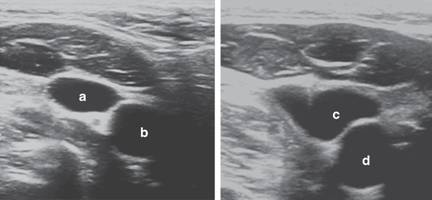

Figura 1: Corte transversal. a. Vena yugular interna derecha (posición anterolateral). b. Arteria carótida común derecha. c. Vena yugular interna derecha en colapso por presión. d. Arteria carótida común derecha.